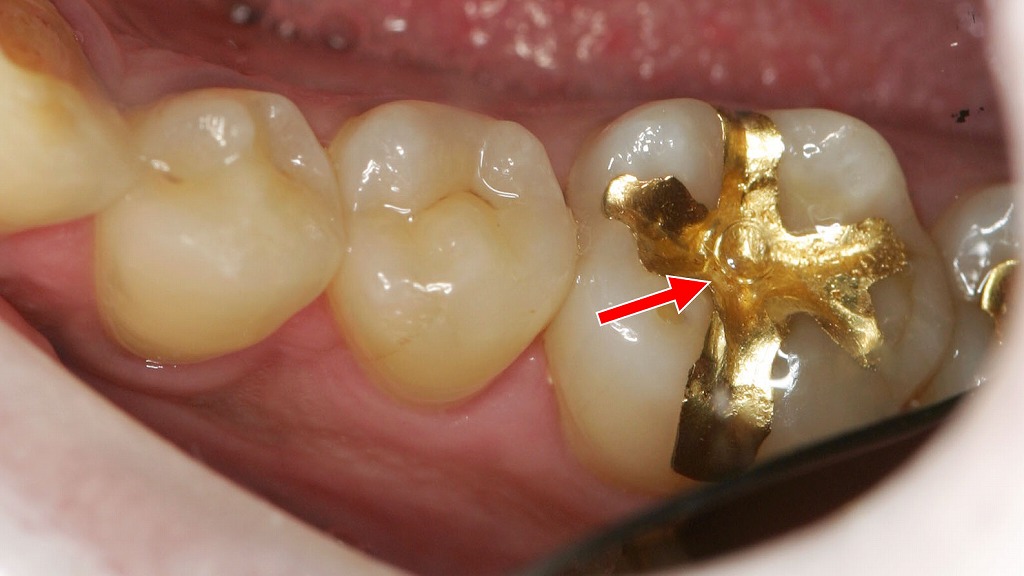

③ ゴールドインレー(自費)

奥歯に装着されたゴールドインレー(ゴールド修復)の症例です。

金合金は歯との適合性が非常に高く、変形しにくいため、長期間にわたり二次虫歯のリスクを抑えられるという特長があります。

また、噛み合わせに調和しやすく、歯への負担が少ないことから、機能性と耐久性を重視した修復治療として現在も高く評価されています。